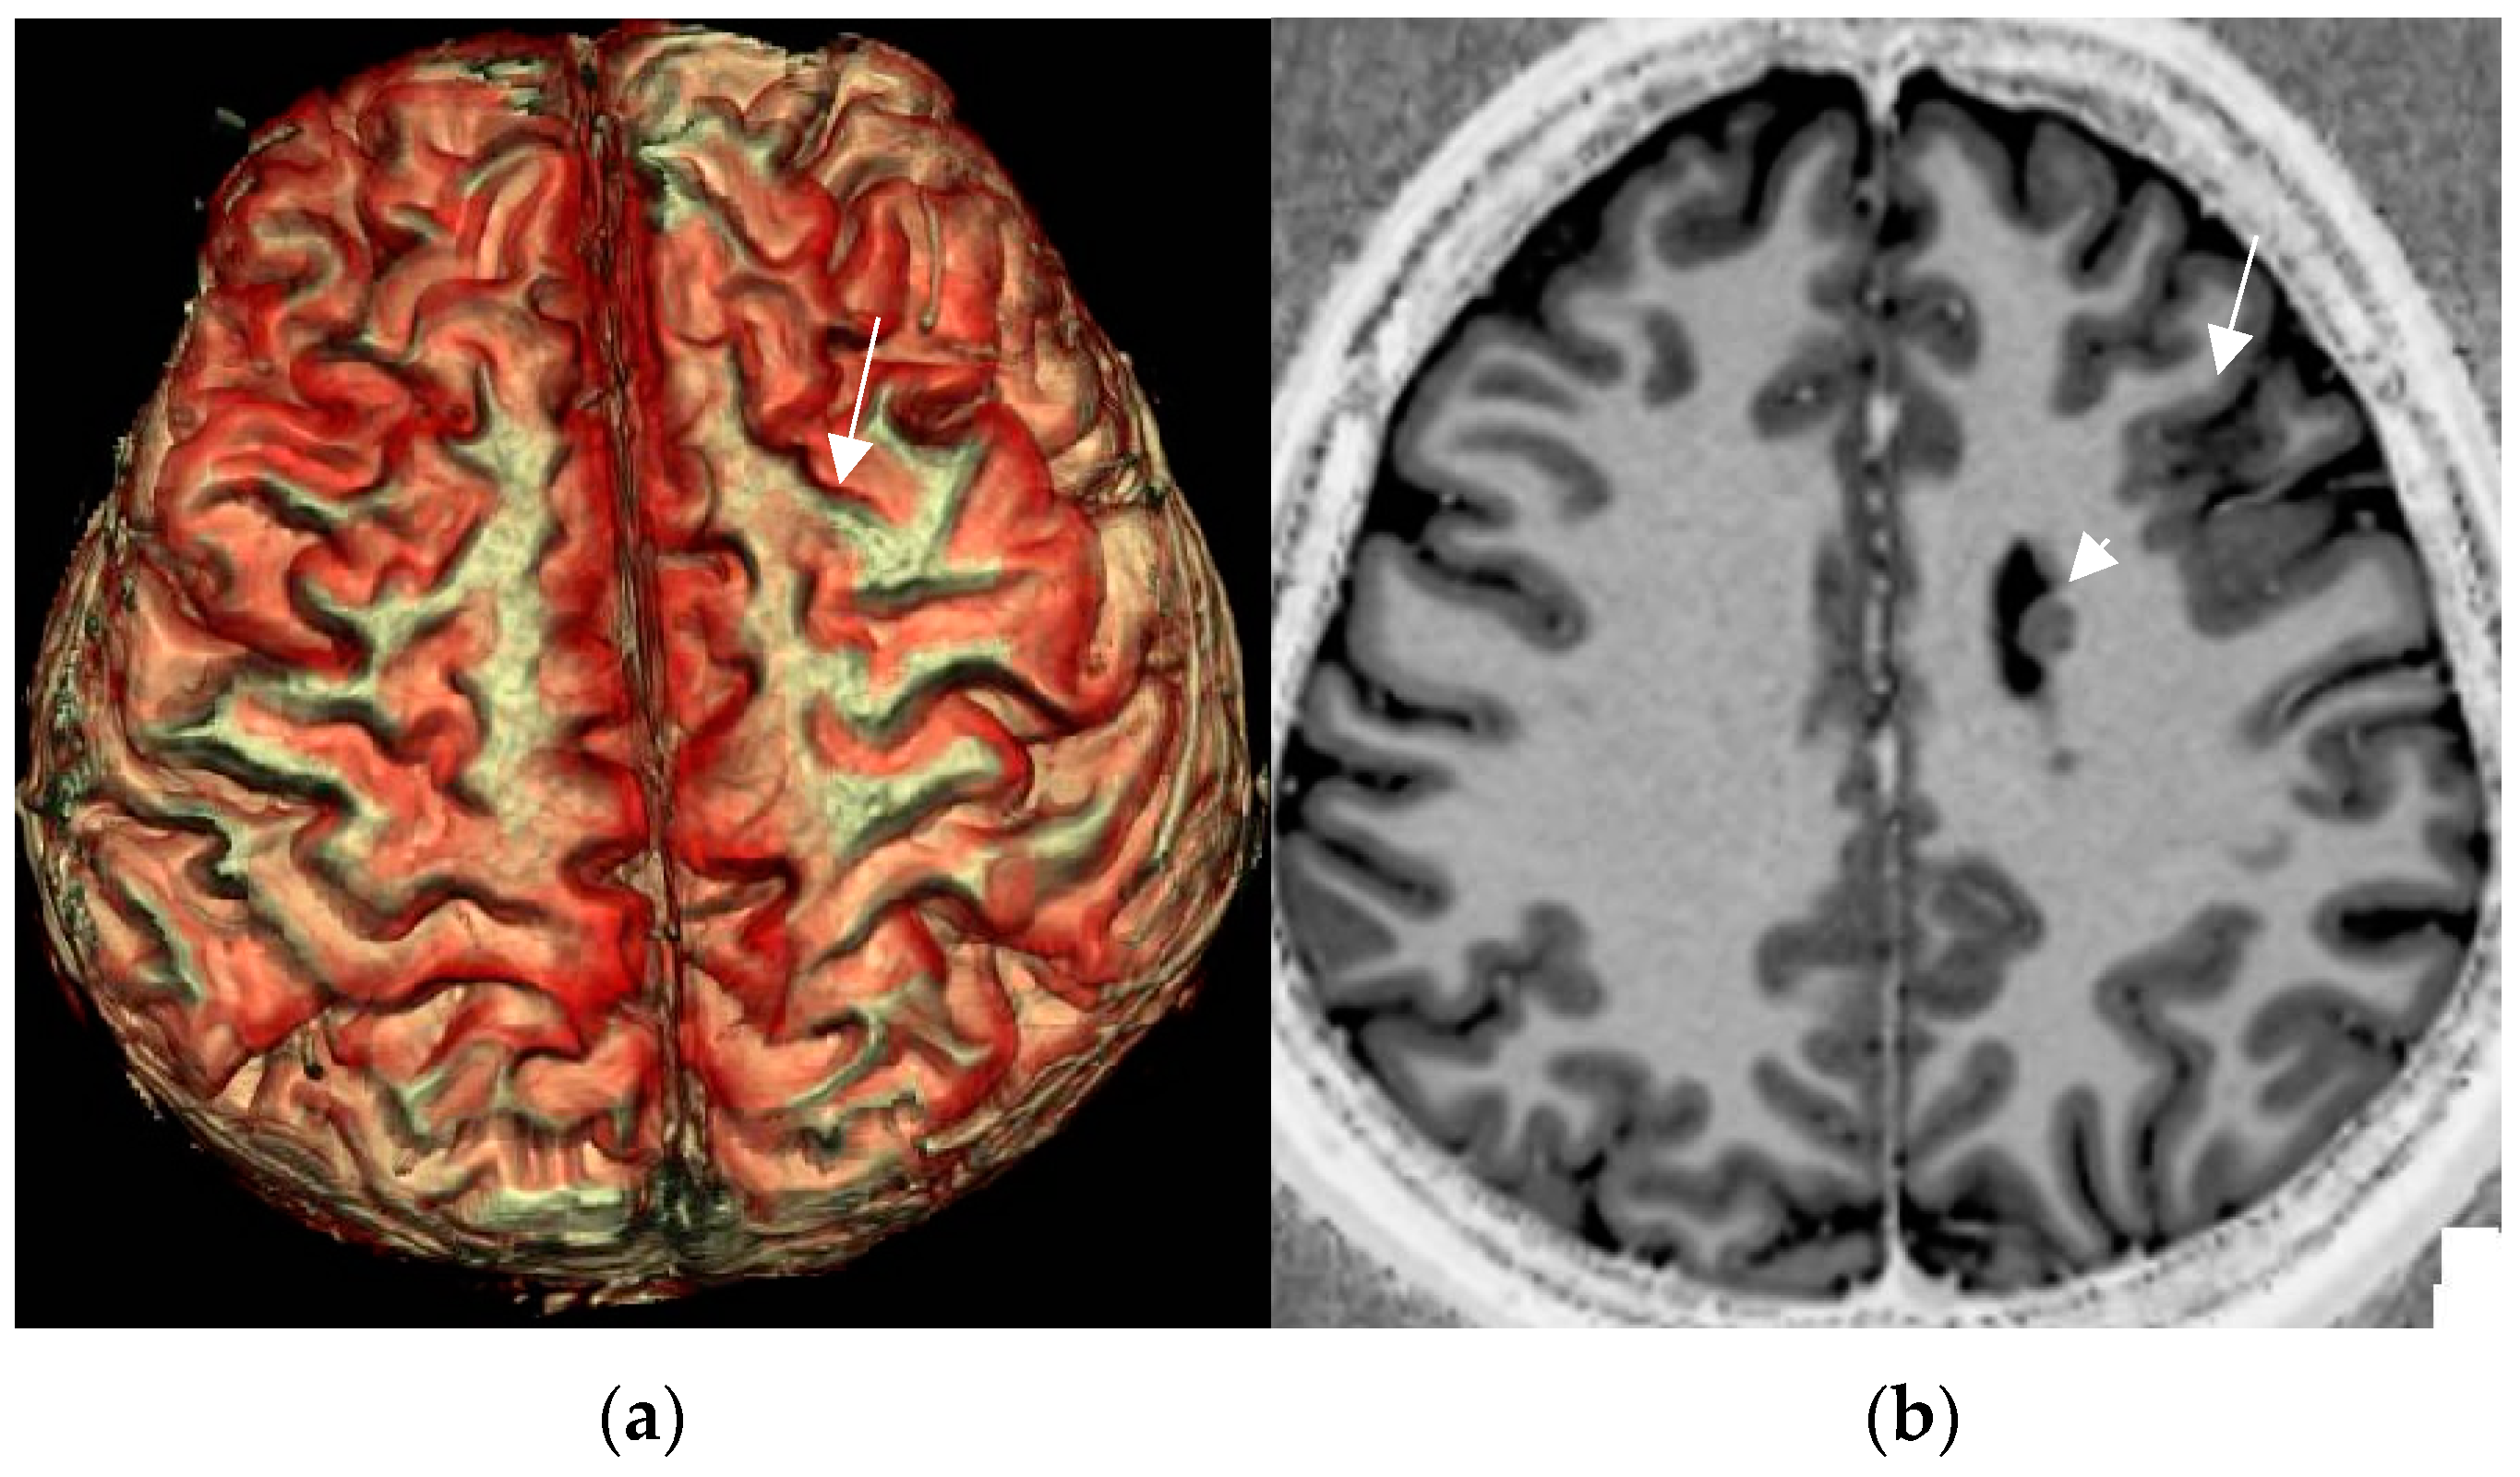

4.8. Postprocessing by 3D Surface Rendering Technique to Improve Comprehension of Superficially Located Lesions

Three-dimensional surface-based reconstruction encompasses the postprocessing of cortical lesions and thus provides a visual depiction of the surface pattern of gyri and sulci (Figure 8). Submillimetric 3D acquisitions are a prerequisite to provide high spatial resolution in order to facilitate visual lesion detection and apply neuronavigation for intraoperative lesion identification.

Figure 8.

3D surface-based reconstruction of cortical folds in left frontal FCD II depicted by a cortical dimple (arrow) on 3D surface-based reconstruction (a). The underlying cause is a left frontal FCD (arrow) in an unusual combination with periventricular nodular heterotopia (arrowhead) depicted on the MP2RAGE sequence (b).

Up to 40% of FCD II are located in the central region. A particular “pattern of the central sulcus” characterized by a focal hook-shaped configuration of the precentral gyrus intersecting the central has been described as an indication of a hidden FCD II [82]. As this sulcal pattern mimics the shape of the power symbol on electronic devices, the term “power button sign” was coined. Though this surface sign is meant to improve presurgical comprehension rather than identification, the power button sign enabled additional detection of centrally located FCD in 6/13 patients with prior negative MRI (46%) [82].